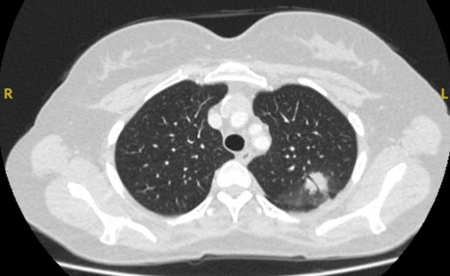

Computed tomography (CT) showing a small peripheral triangular nodule in the right lower lobe, consistent with an intrapulmonary lymph node

From the collection of Dr George Tsaknis, MD, PhD, FRCP(London), MRQA, MAcadMEd, PGCert; used with permission